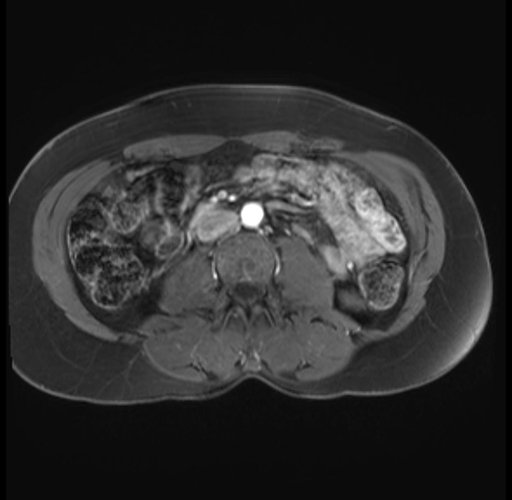

Imaging Analysis

Look through the patient's CT scan to identify any areas of concern for the necessary procedure.

Based on your CT findings, which issue(s) are present and would give reason for "planned slowing down moment(s)" in this case?